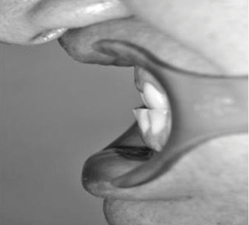

Fig 13. Pretreatment lateral (Fig 11) and posteroanterior (Fig 12) cephalometric x-rays, along with a lateral overjet image (Fig 13). Maxillary deficiency was present in the transverse and sagittal planes.

Figure 13